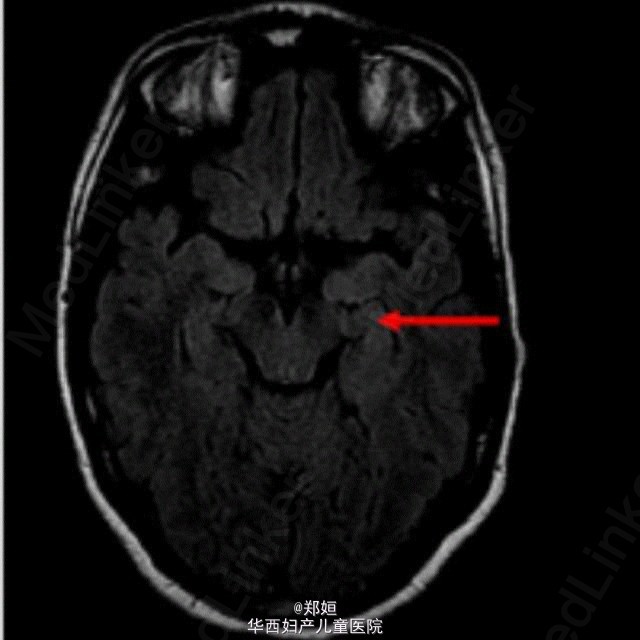

最近看的一个病例,给大家分享。 27岁女性,因出现幻觉入院。 既往:10天前出现流感样病症。 神经科检查示患者有顺行性遗忘症状和行动障碍,格拉斯哥昏迷评分从10分降到6分,全身CT检查示右侧卵巢有直径4cm的囊性包块。